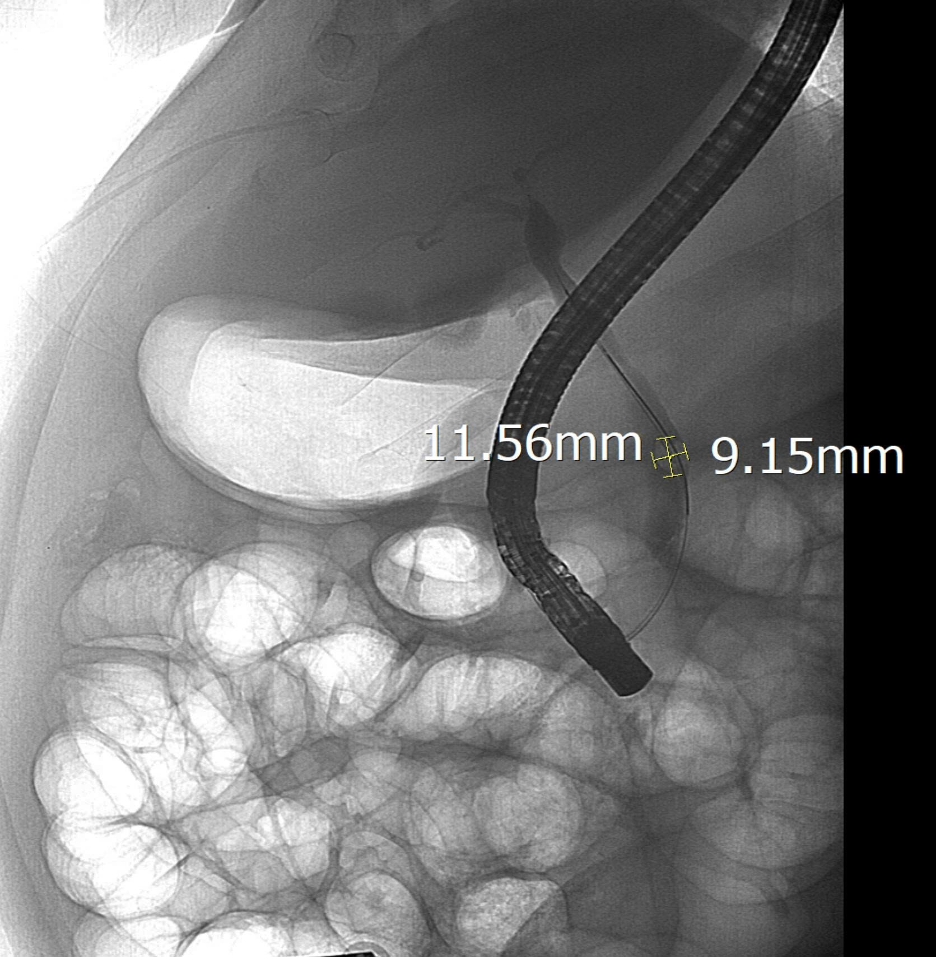

Sỏi ống mật chủ của bệnh nhân được phát hiện khi chụp DSA tại Bệnh viện Hữu nghị Việt Xô.

Trong quá trình can thiệp, ê-kíp đã lấy thành công viên sỏi kích thước 11,5 x 9 mm, giải phóng tình trạng sỏi ống mật chủ cứu sống bệnh nhân kịp thời.

Viên sỏi lớn trong đường ống mật chủ của bệnh nhân được can thiệp thành công